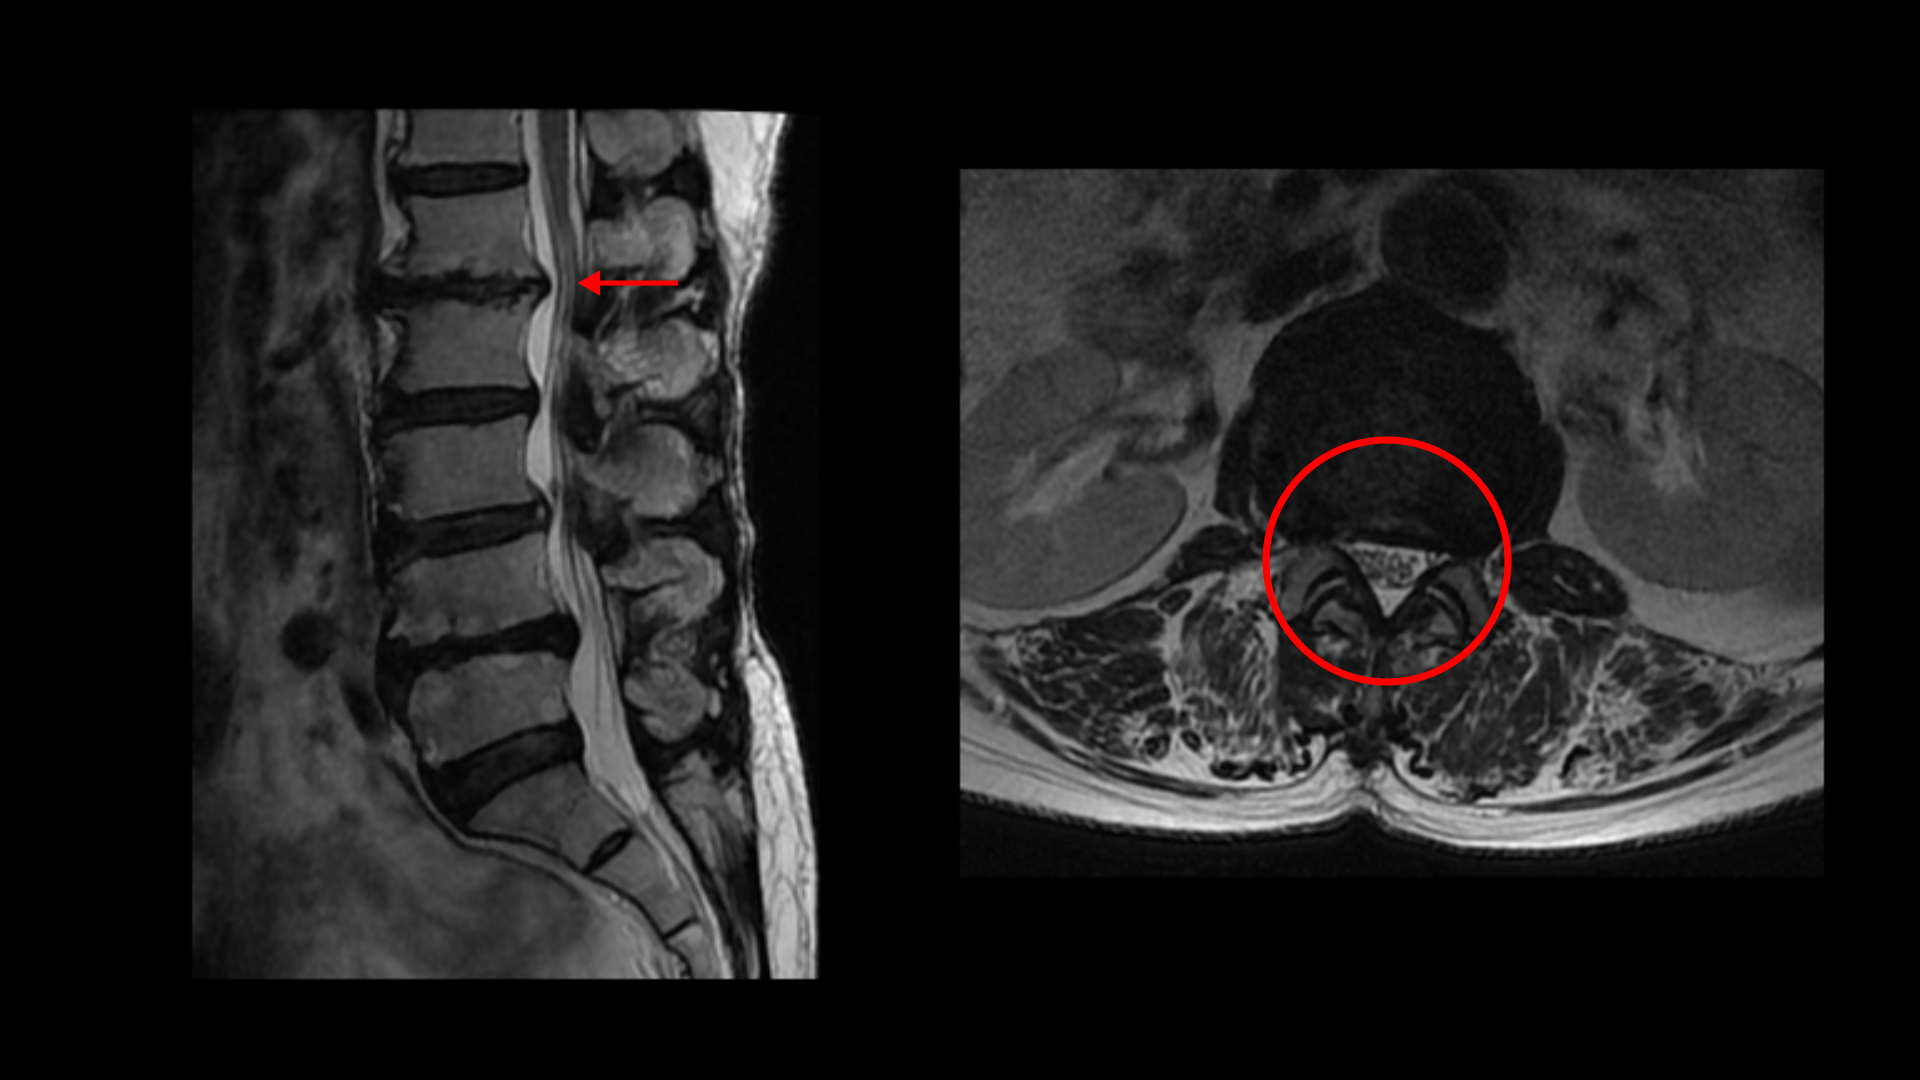

이분 MRI를 보면 허리 다섯 마디에 전부 퇴행성 디스크가 있습니다.

1-2번에는 오른쪽으로 디스크도 밀려 나와 있고 중심성 협착도 있습니다.

2-3번에는 왼쪽으로 신경구멍 쪽으로 디스크가 밀려 나와있습니다.

3-4번에는 중심성 협착이 있고

4-5번에는 왼쪽으로 디스크가 밀려 나와있고 심한 중심성 협착과 왼쪽 추간공협착도 있습니다.

5-1번에는 왼쪽으로 디스크가 밀려 나와있고 전반적으로 왼쪽이 상태가 더 안 좋은데 이분의 증상도 왼쪽 엉덩이와 다리의 통증과 저림 및 마비감입니다.